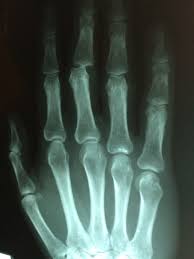

Radiodiagnóstico é a especialidade médica que utiliza técnicas de imagem para visualizar estruturas e órgãos internos do corpo humano. Essas imagens são obtidas por meio de radiações ionizantes (como raios-X) ou técnicas não ionizantes (como ultrassom e ressonância magnética).

As técnicas mais comuns utilizadas no radiodiagnóstico incluem radiografias convencionais, ultrassonografias, tomografias computadorizadas (TC), ressonâncias magnéticas (RM) e medicina nuclear. Cada uma dessas técnicas tem suas próprias indicações e capacidades de imagem.